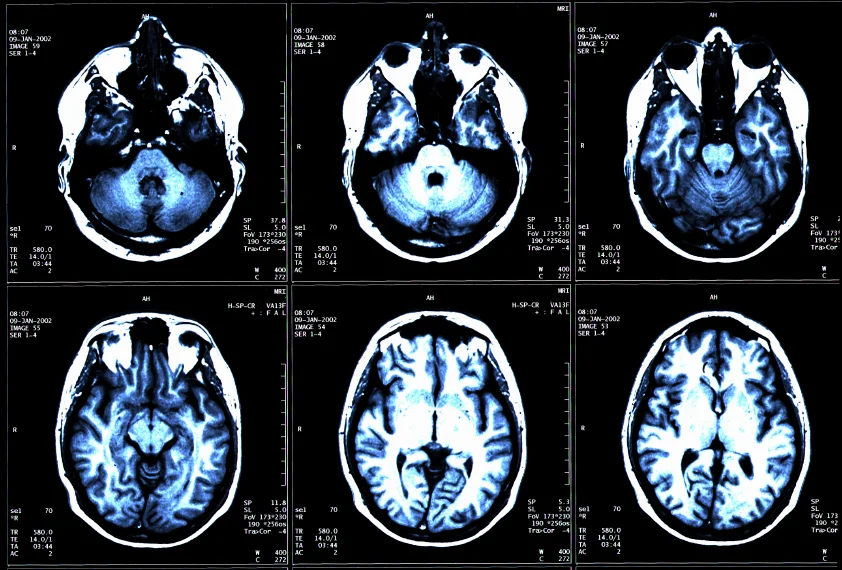

/Multiple sclerosis is an autoimmune disease that affects the brain and spinal cord. It typically affects more women than men and is most commonly diagnosed between ages 20 and 40.